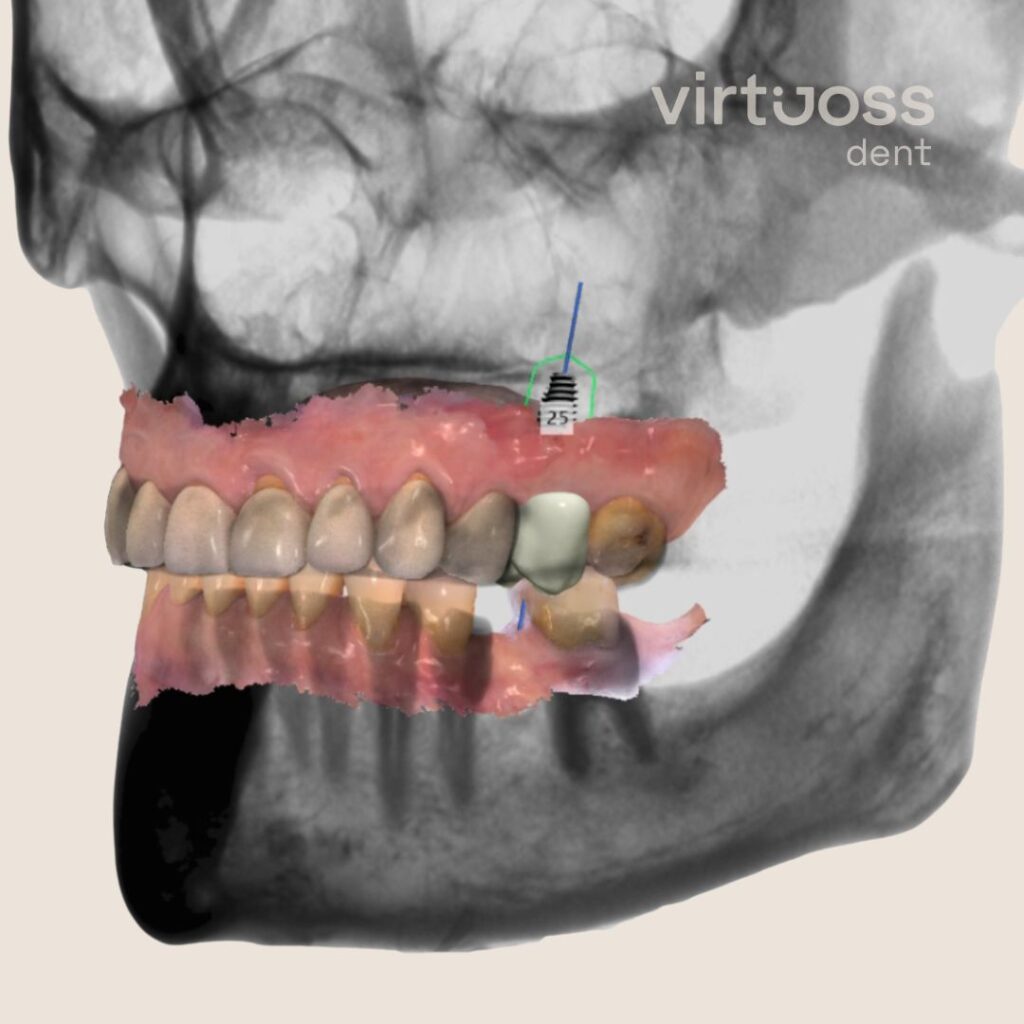

Výše zmíněné 3D rentgeny (CT skeny) jsou navíc zásadní pro plánování implantátů. Díky těmto informacím vytvoříme léčebné plány a zubní náhrady, které vám budou sloužit roky.